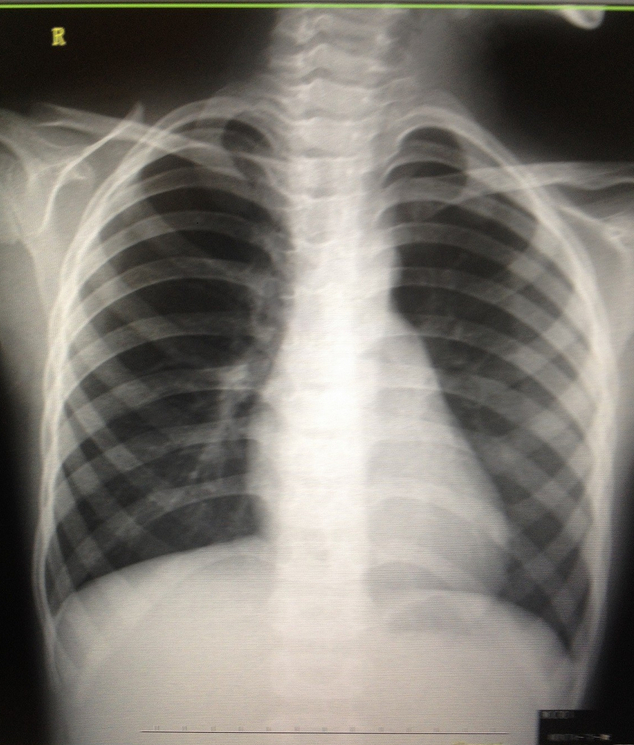

7岁小孩,咳嗽3天,看看左中下肺及肺A段